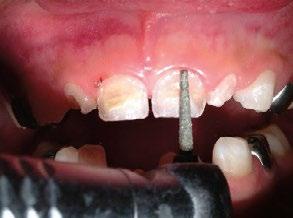

Figura 1. Foto inicial de la paciente.

Paciente femenina de 3 años de edad que requiere rehabilitación de los incisivos superiores, la madre de la paciente solicita que el tratamiento sea lo más conservador y estético posible.

El requerimiento estético por parte de la madre de la paciente es fundamental para la decisión de la confección del plan de tratamiento, selección del material y preparación de la restauración (Figura 1).

Se inicia la preparación con desgaste mínimo de las superficies vestibulares con fresa diamantada de punta redondeada, el desgaste es mínimo solo tratando de hacer más uniforme la superficie, ya que el grosor de las carillas será de aproximadamente .5 mm, en el área cervical vestibular se realiza una terminación

Figura 2. Preparación.

tipo “chaflán”, en los incisivos laterales se retira lesión cariosa con fresa de bola diamantada del núm. 6 (Figura 2).